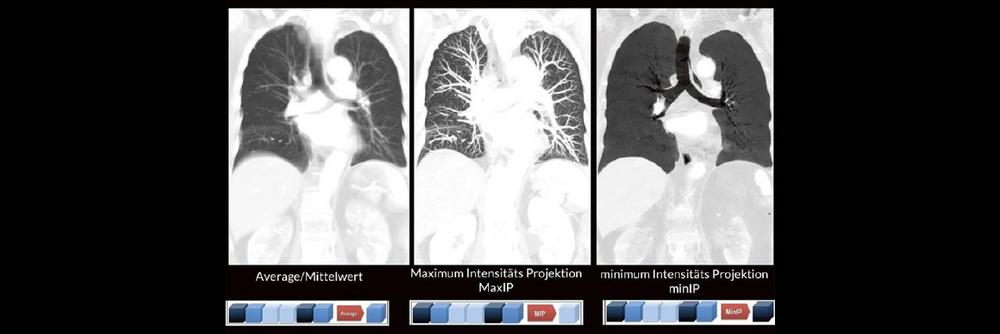

Bildnachverarbeitung in der CT (Webinar | Online)

Alex Riemer Moderne CT-Scanner unterstützen die Anwenderinnen und Anwender bei der Durchführung der meisten CT-Untersuchungen. Hierzu zählt auch das automatische Erstellen von streng coronalen und […]